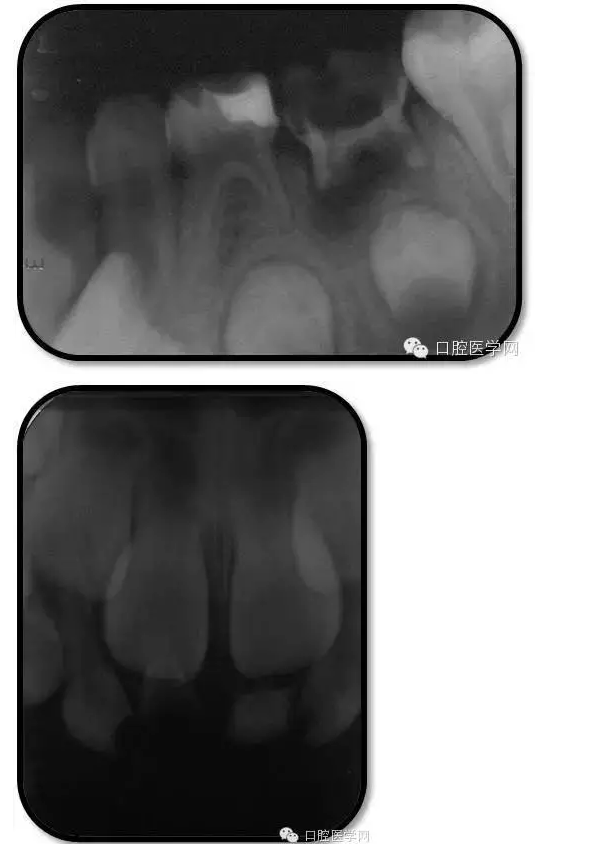

臨床檢查: 75OL齲洞, 舌側(cè)牙體完全劈裂斷端齊齦,探及大量軟化腐質(zhì)。頰側(cè)牙齦紅腫見瘺管,擠壓大量溢膿。叩(±),不松動。X線:75根管空虛,牙根吸收約1/2,根尖周及根分歧大面積透射影,35發(fā)育4期,骨硬板尚連續(xù);51殘根,唇側(cè)牙齦瘺管,叩(±),不松動。X線:51牙根吸收約1/2,根尖周低密度影。

85O、84DO充填體邊緣不密合,叩(±),不松動。84頰側(cè)牙齦略紅腫。X線:84遠(yuǎn)中根及髓室底完全吸收,根分歧透射影,近中根內(nèi)側(cè)見外吸收,44上方骨硬板連續(xù)。85近中根完全吸收,髓室底吸收,根分岐透射影,遠(yuǎn)中根管內(nèi)見根充影像。45發(fā)育4期,骨硬板連續(xù)。

85O、84DO充填完好,邊緣密合,叩(-),不松,齦無紅腫。X線:84、85根分歧透射影,44、45骨硬板連續(xù),恒牙胚上方骨板厚約2-3mm。75帶環(huán)絲圈式間隙保持器完好,無松動,無咬合不適。64MO中齲。 64MO中齲去腐凈,自酸蝕,SEBOND,樹脂充填。 口腔衛(wèi)生宣教,囑3個月后復(fù)診。

1、根分歧處病變姑息保留牙的治療及轉(zhuǎn)歸。 75牙體缺損過大,根分岐大面積透射影并累及根尖周。故拔除后間隙保持。84、85初診時已做過根管治療,有繼發(fā)齲,牙根吸收較多,可見大面積的根分歧病變,但根尖無病變,考慮44、45表面骨硬板連續(xù),故只對患牙進(jìn)行了繼發(fā)齲充填治療,姑息保留。3個月復(fù)查時,85O、84DO充填完好,邊緣密合,叩(-),不松,齦無紅腫。7個月復(fù)查時85O、84DO充填完好,邊緣密合,叩(-),不松,齦無紅腫。X線:84、85根分歧透射影,44、45骨硬板連續(xù)。 回顧整個治療過程,應(yīng)定期復(fù)查84、85姑息保留牙,且間隔時間不宜過長。觀察根分歧病變的恢復(fù)情況,一旦發(fā)現(xiàn)恒牙胚受累及,則需采取積極措施。